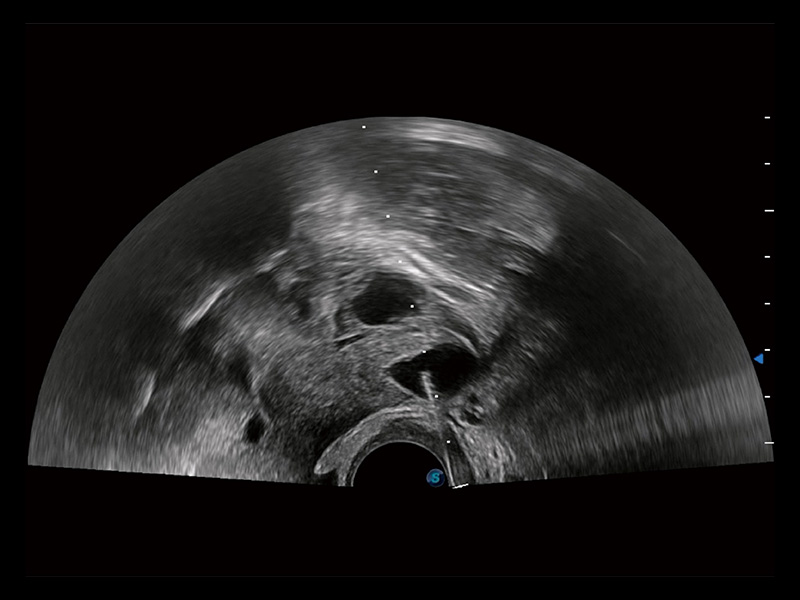

窥器式探头

采用弯柄探头替代窥器下叶,巧妙实现了实时超声监控下的单人手术操作。探头频率高、图像清晰,不受肥胖影响,使得手术过程中无需充盈膀胱,即可有效进行胚胎移植、减胎手术的精准操作。

临床图

超声引导下胚胎移植